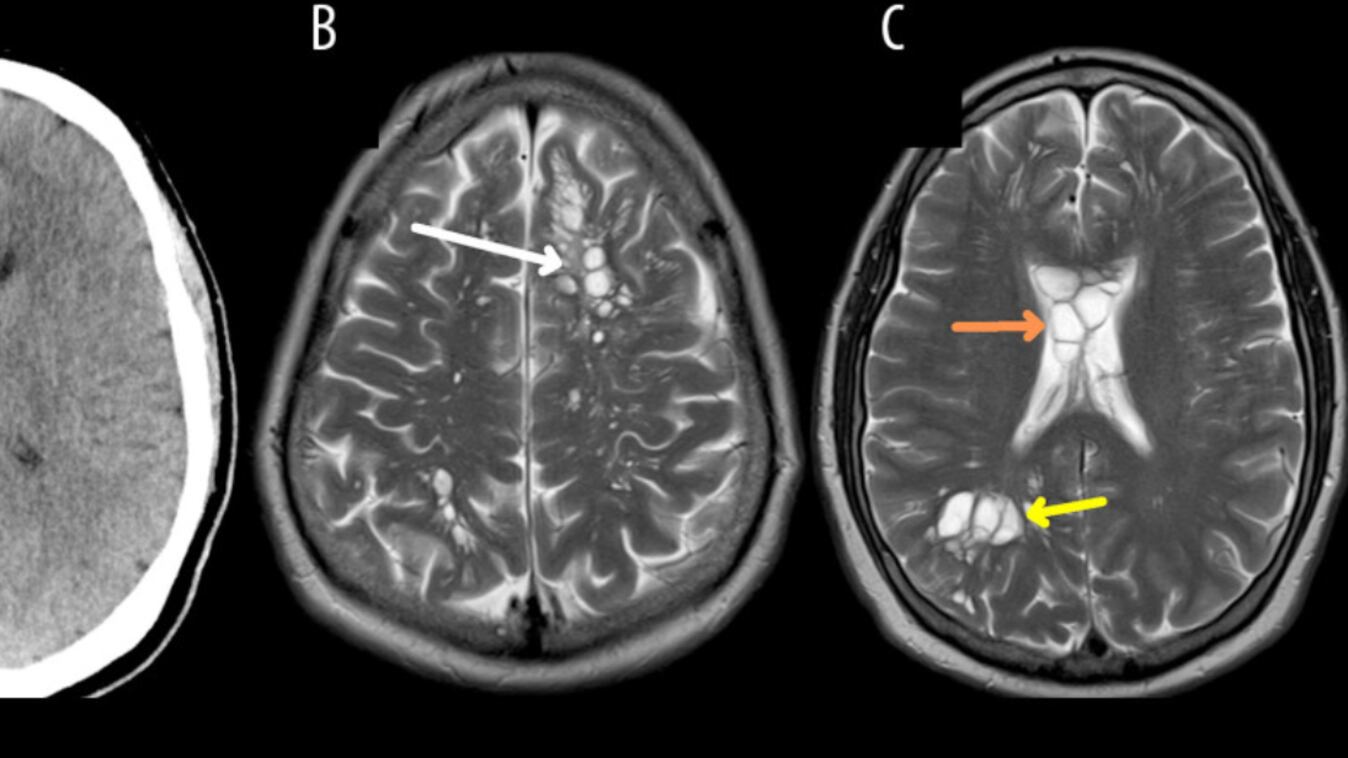

Según el reporte de CNN, el médico le hizo una tomografía que reveló múltiples quistes en todo el cerebro. Ante la sospecha inicial de que pudiera padecer una enfermedad neurológica extraña denominada quistes neurogliales congénitos, los médicos le ingresaron en un hospital de Orlando para consultar con neurocirugía.

Y bueno, los exámenes que ahí le practicaron, arrojaron que los quistes eran larvas, que se instalaron en el cerebro y le causaron una infección denominada neurocisticercosis.